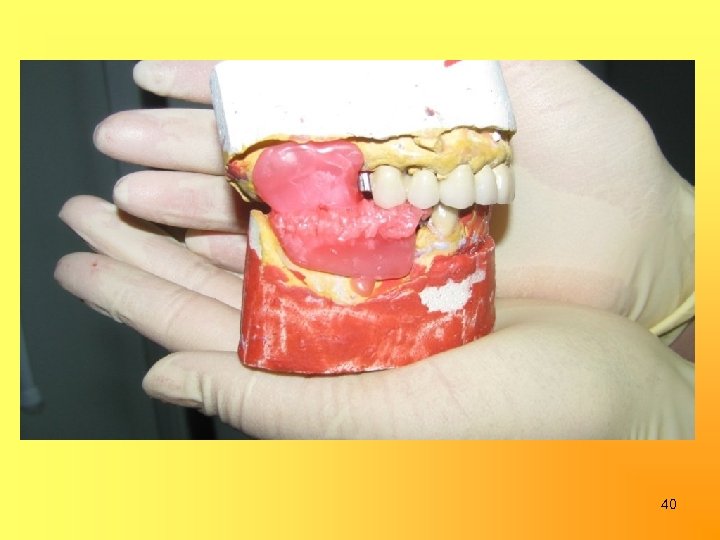

Изготовление бюгельных протезов в/ч и н/ч с замковыми креплениями на 15, 24, 43 и опорно-удерживающими кламмерами на 37 и 35 35

40